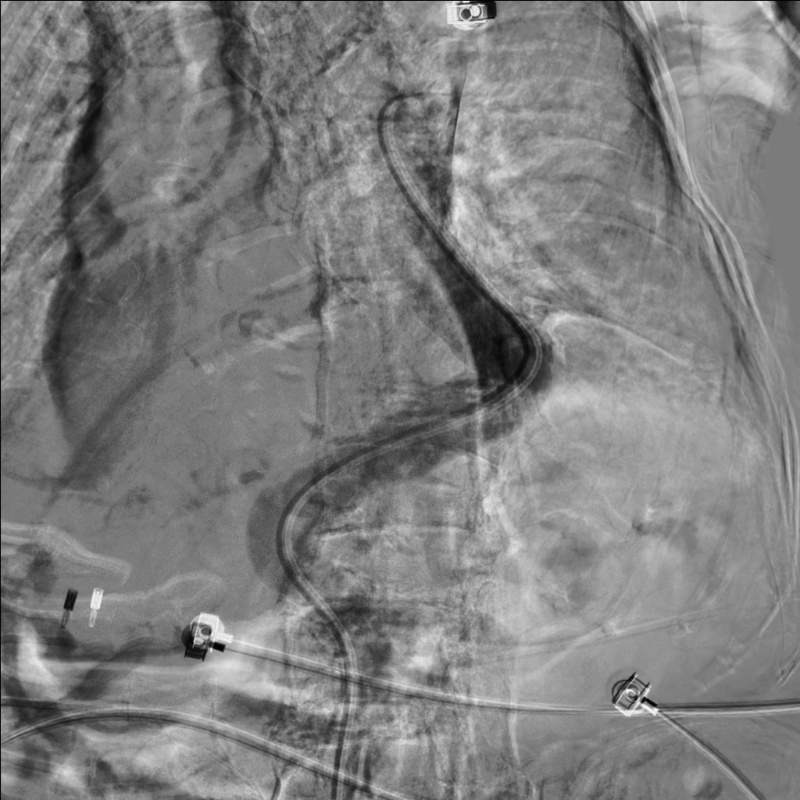

术中造影显示胸腹主动脉呈现2个S型弯曲,RH造影导管插入腹腔干非常困难,无法找到腹腔干。

更换造影导管及反复尝试后,导管进入腹腔干动脉。

造影显示肝总动脉发出胃十二动脉及肝左右动脉。但胃十二指肠多处弯曲,微导管进入胃十二指肠动脉远端困难,更换成超细导丝后最后将微导管送入胃十二指肠动脉远端。

经微导管注入栓塞剂到胃十二指肠动脉全程,造影显示胃十二指肠动脉栓塞彻底,肝内动脉分支血运良好无副栓塞。